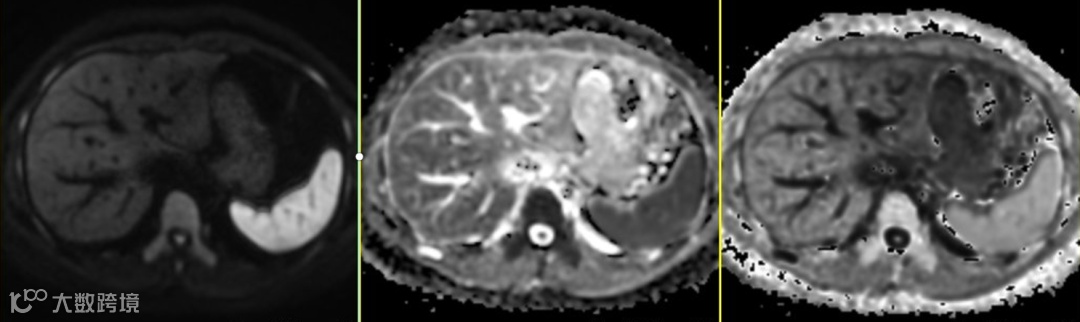

脾脏是一个血供极其丰富的器官,含有大量的“液体”。血液和细胞外液本身具有很长的T2弛豫时间。因此,脾脏在常规T2WI上本身就是显著高信号,如上图△1。

由于DWI序列是基于T2加权的参数的,这种固有的本底T2高信号会“透射”到DWI图像上,导致脾脏在DWI上即使在没有扩散受限的情况下也表现为高信号,如上图△2。

b值越小(腹部扫描中本身选取的扫描b值就不高),这种“透射效应”则表现得越明显,上图△3为b值=0的图像。